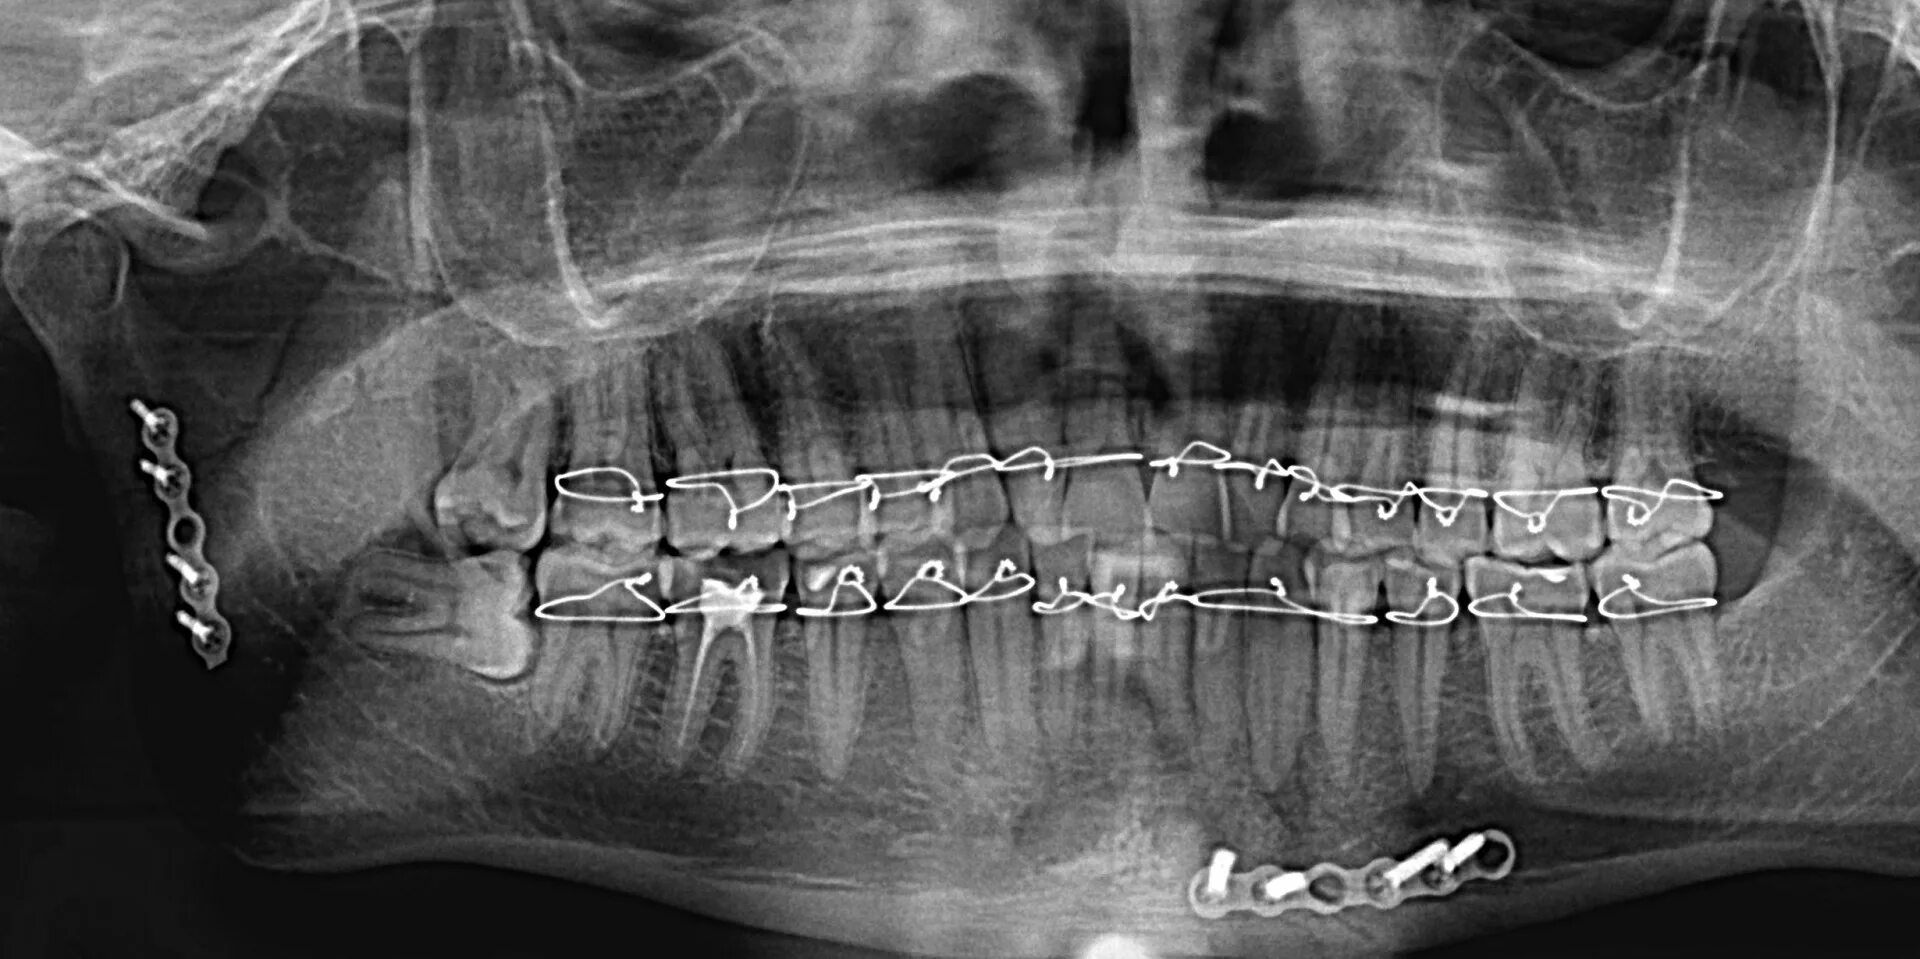

Переломы челюстей студфайл